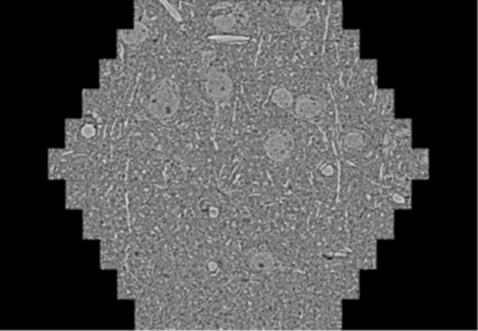

鼠脑切片。165 μm ×143 μm 面积区域成像,耗时仅需1.5秒。

1 mm3人脑皮层组织进行高分辨成像,并对其中的各种细胞结构进行三维重构分析。